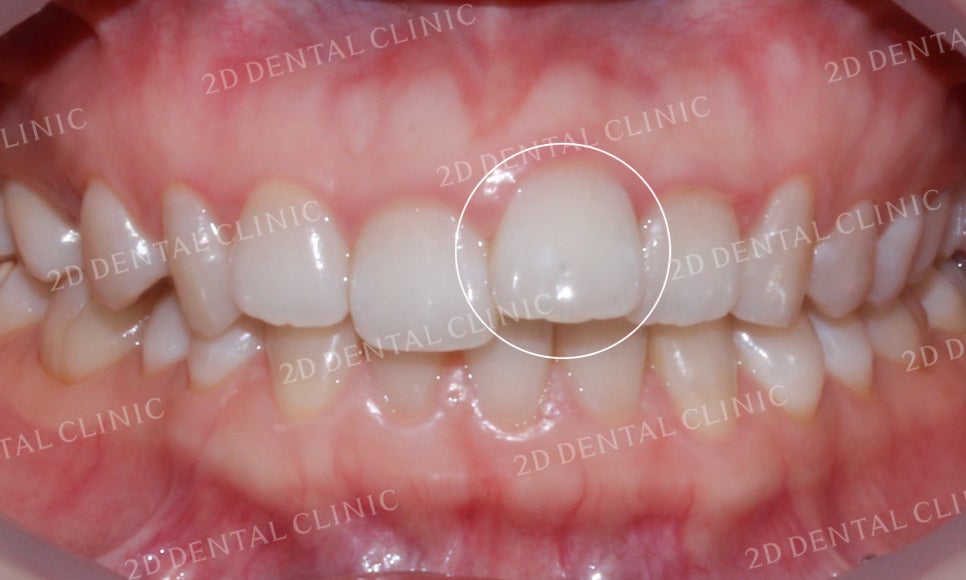

"덧니치아 교정 전"

덧니치아 투디교정 전

[투디교정] 덧니교정, 앞니교정으로 치열을 고르게! by.투디치과(2D치과)

덧니치아 교정 전

입술의 모습을 보시면

상악 중절치의 덧니 증상으로 인해

윗입술이 미세하게 돌출된 모습입니다.

미소 시 전치의 모습입니다.

상악 좌측 중절치가 앞쪽으로

강하게 뻐드러진 모습이 확인됩니다.